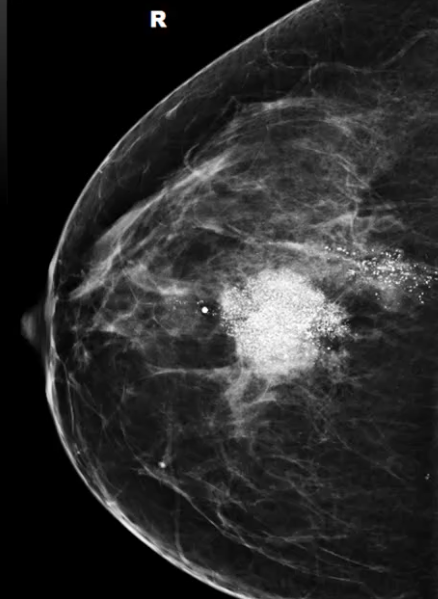

What is this an image of?

Mass with calcifications

Abnormal calcifications within the breast